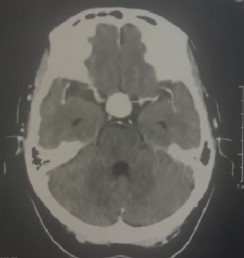

Estudios imagenológicos: los estudios tomográficos indicaron aneurisma sacular de la arteria carótida interna supraclinoidea derecha asociado a remodelación ósea (Figuras 1 y 2). Mientras que la resonancia magnética nuclear (RMN) de hipófisis mostró dilatación sacular aneurismática que ocupa la silla turca con extensión supraselar, dependiente de la arteria carótida derecha.

Figura 1 Aneurisma sacular en tomografía cerebral por contraste